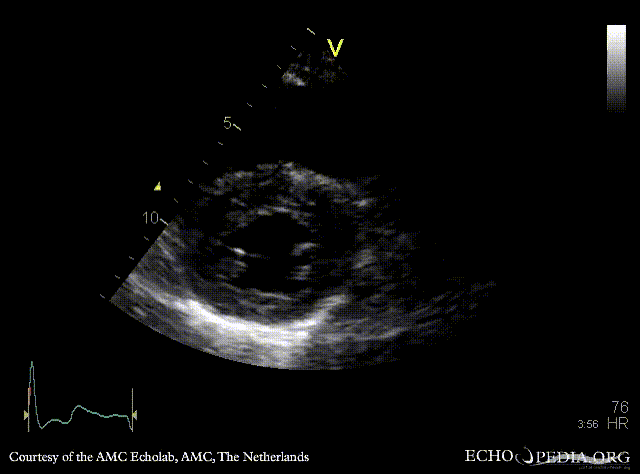

| PLAX: concentric hypertrophy of left ventricle, thickend aortic valve | PSAX: concentric hypertrophy of left ventricle |